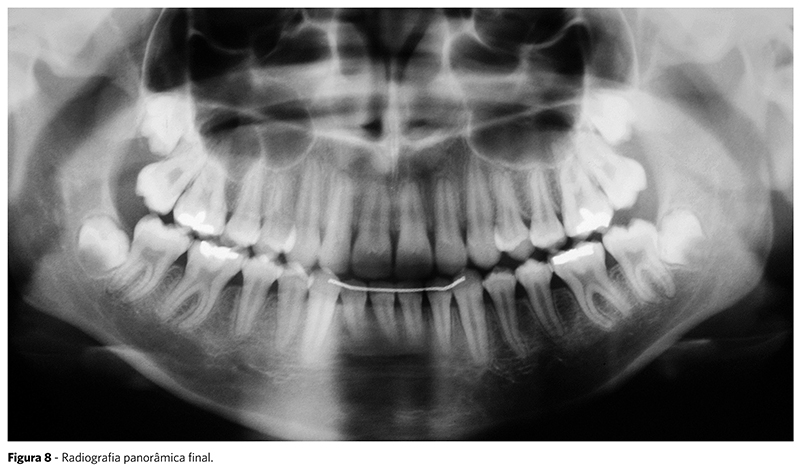

Na radiografia panorâmica final, observa-se certo grau de reabsorções radiculares, porém compatíveis com o tratamento ortodôntico (Fig. 8).